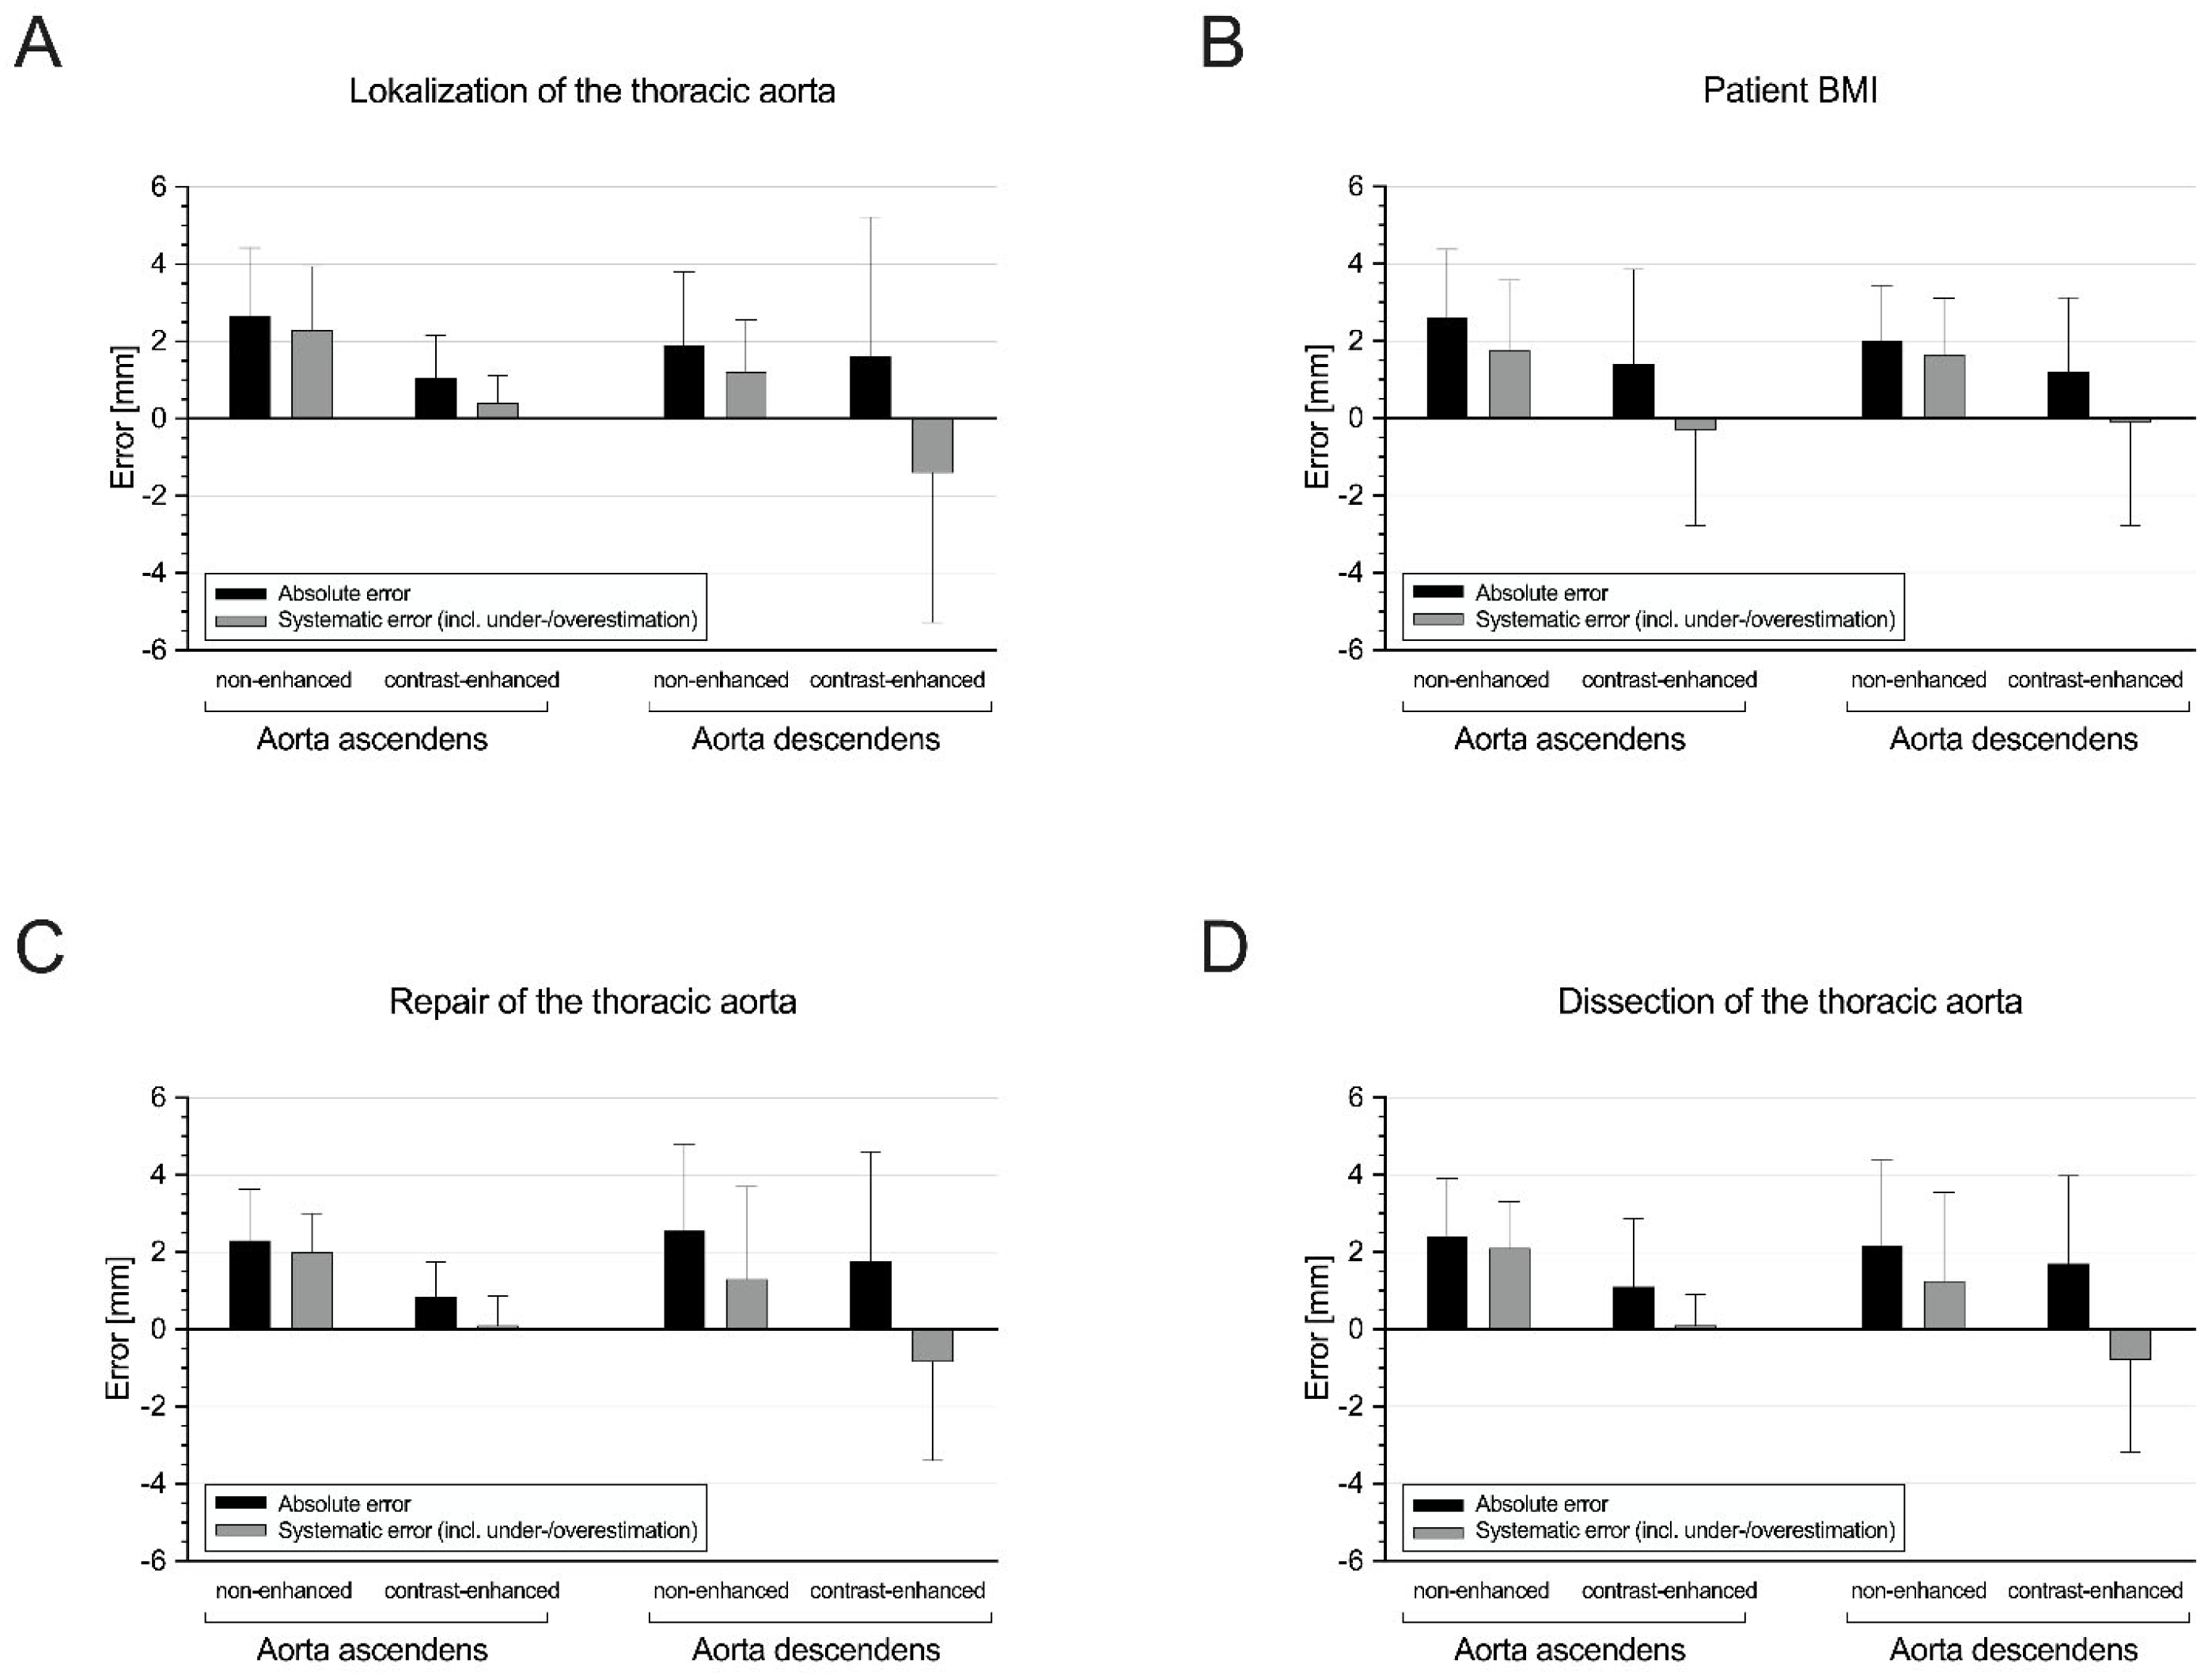

3.3. Subgroup I: Ascending Aorta vs. Descending Aorta

3.4. Subgroup II: Non-Obese vs. Obese Patients

3.5. Subgroup III: Patients without vs. with Prior Aortic Repair

3.6. Subgroup IV: Patients without vs. with Aortic Dissection